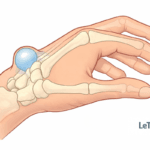

Syndrome du canal carpien

Ce syndrome est causé par une compression du nerf médian dans le canal carpien. Il entraîne :

- douleurs nocturnes,

- engourdissements dans les doigts,

- perte de force musculaire.

Il touche majoritairement les femmes après 40 ans.

Fourmillements, engourdissements

Ces symptômes neurologiques (paresthésies) sont typiques du syndrome du canal carpien ou d’une compression nerveuse.